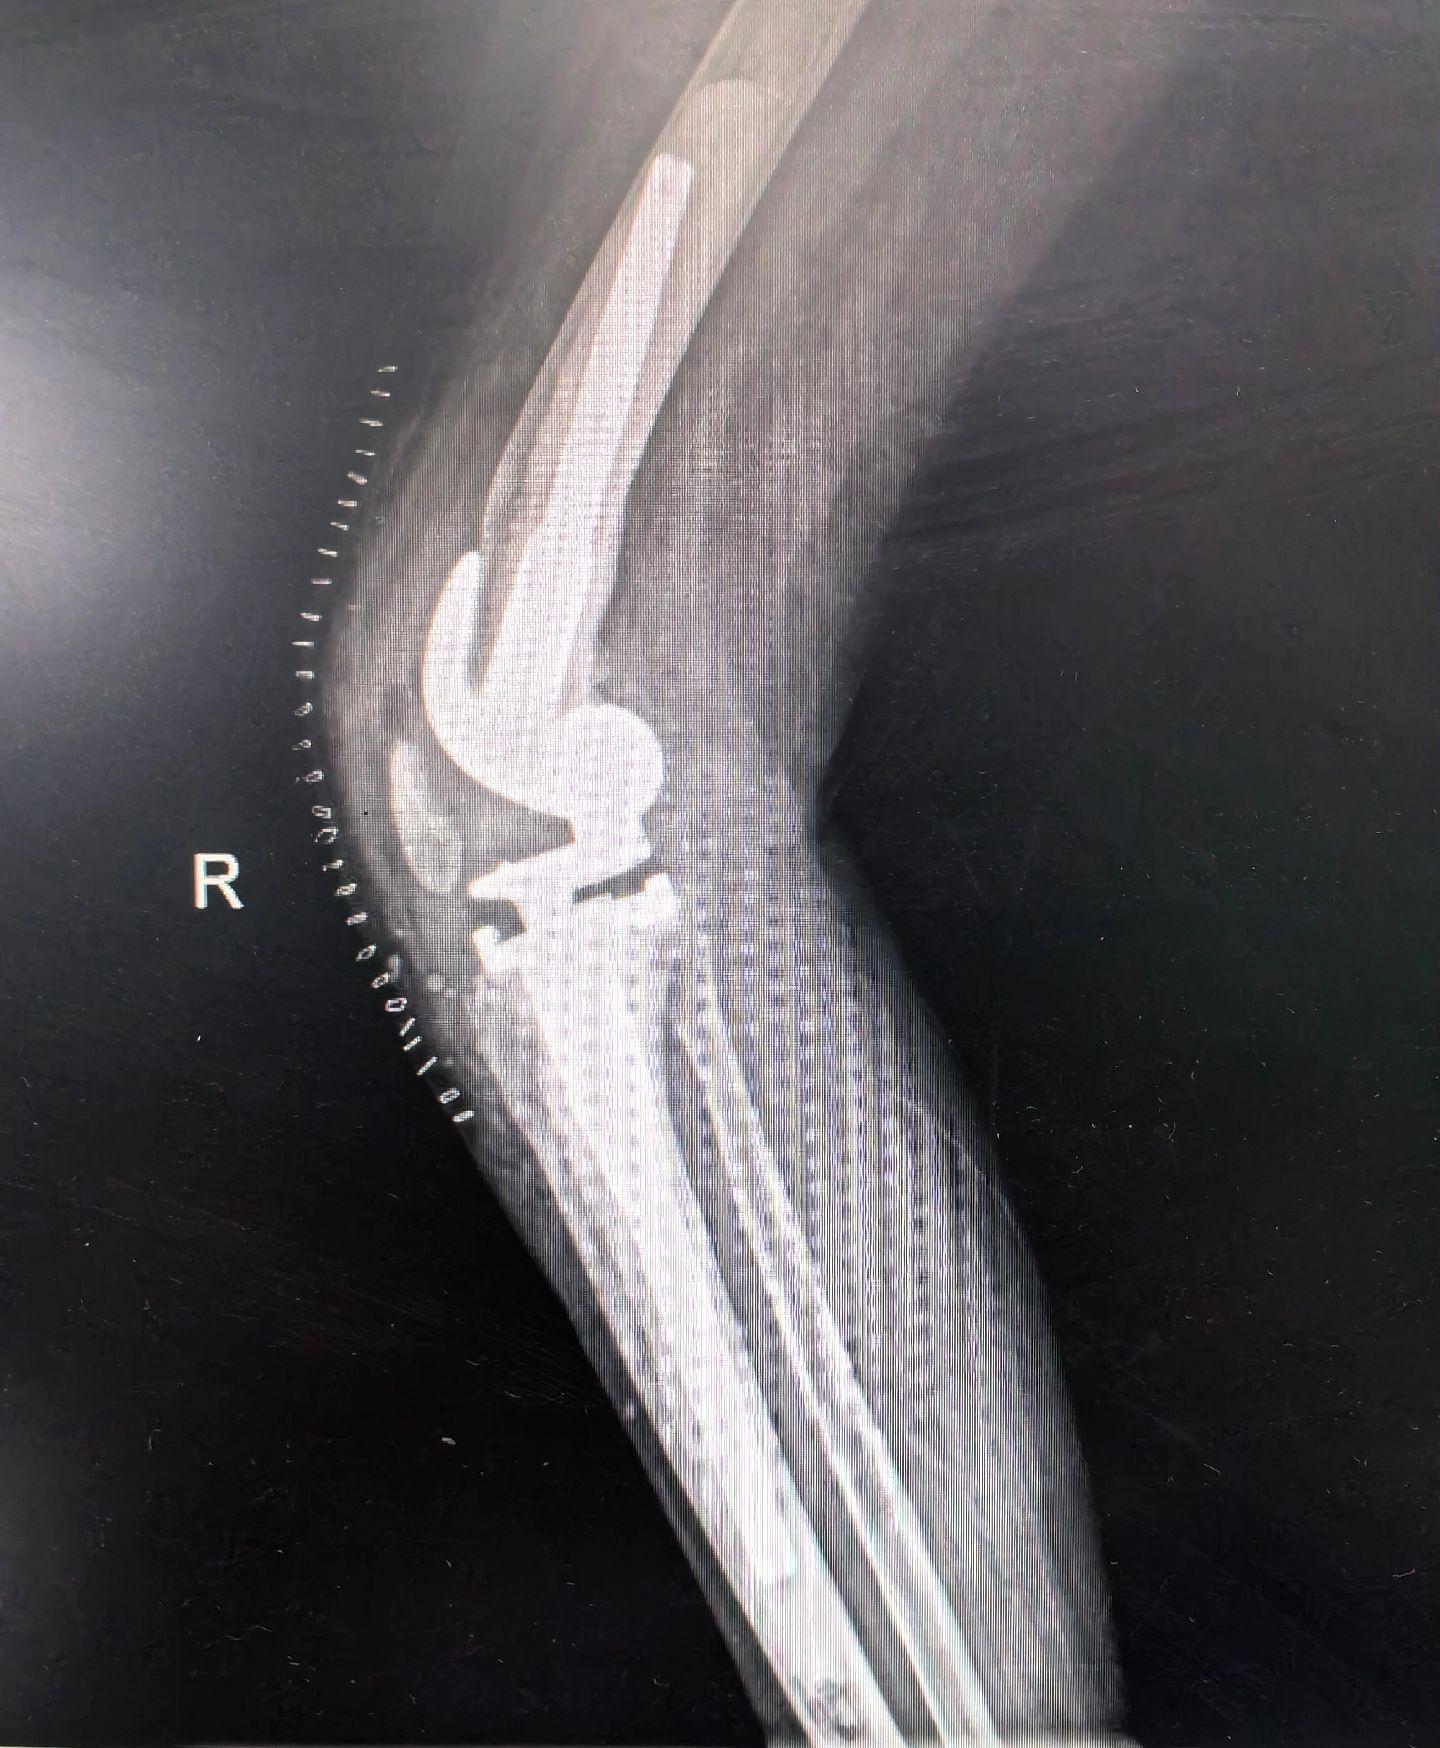

膝关节翻修。PJI,二期翻修。关节置换,谨防感染。